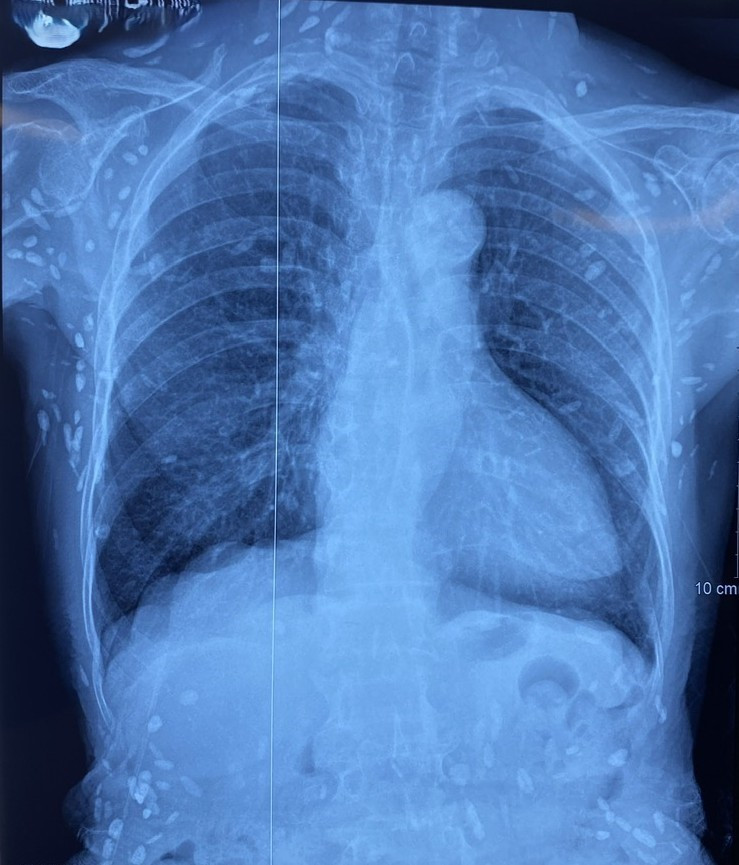

Người bệnh được chuyển lên từ tuyến trước vì rối loạn ý thức đe dọa suy hô hấp, hình ảnh cắt lớp vi tính sọ não và X-quang ngực cho thấy rất nhiều nốt cản quang trong nhu mô não và dưới da vùng ngực-bụng.

Nhiều nốt cản quang dưới da thành ngực-bụng và chi trên - Ảnh BVCC

Người bị nhiễm sán lợn do ăn phải nang sán trong thịt lợn gạo không nấu chín hoặc trứng sán có trong rau sống. Ở người, ngoài vị trí cơ, nang sán có thể được hình thành tại các vị trí nguy hiểm như não, mắt, có thể gây ra các triệu chứng tại cơ quan này như động kinh, rối loạn tâm thần – vận động, đau đầu, đau mắt, giảm thị lực…

Nang sán dây lợn có thể tự thoái hóa hoặc bị vôi hóa, tạo nên nhiều hình ảnh cản quang phát hiện được trên phim X-quang như trường hợp bệnh nhân trên.